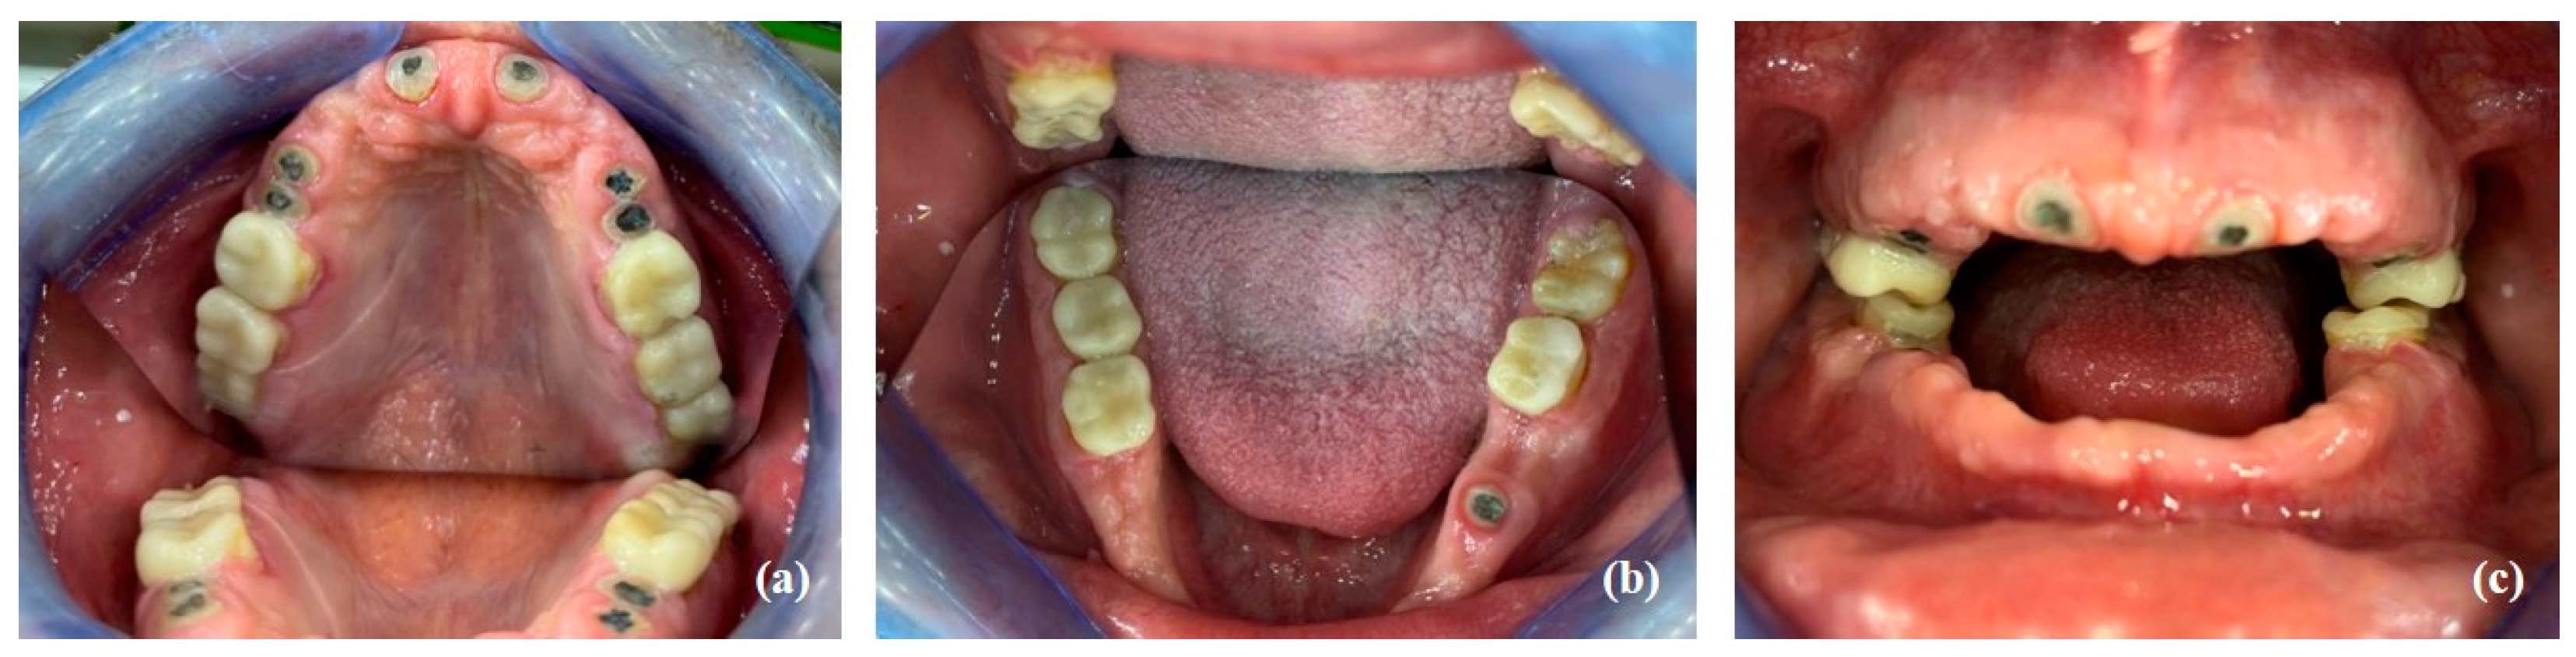

2.1. Clinical and Radiological Examination